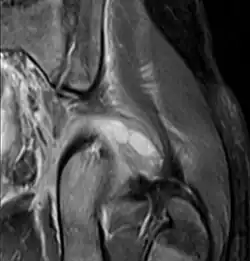

![]() | |

| Transverse T2 magnetic resonance imaging section through the hip region showing abscess collection in a patient with pyomyositis. | |